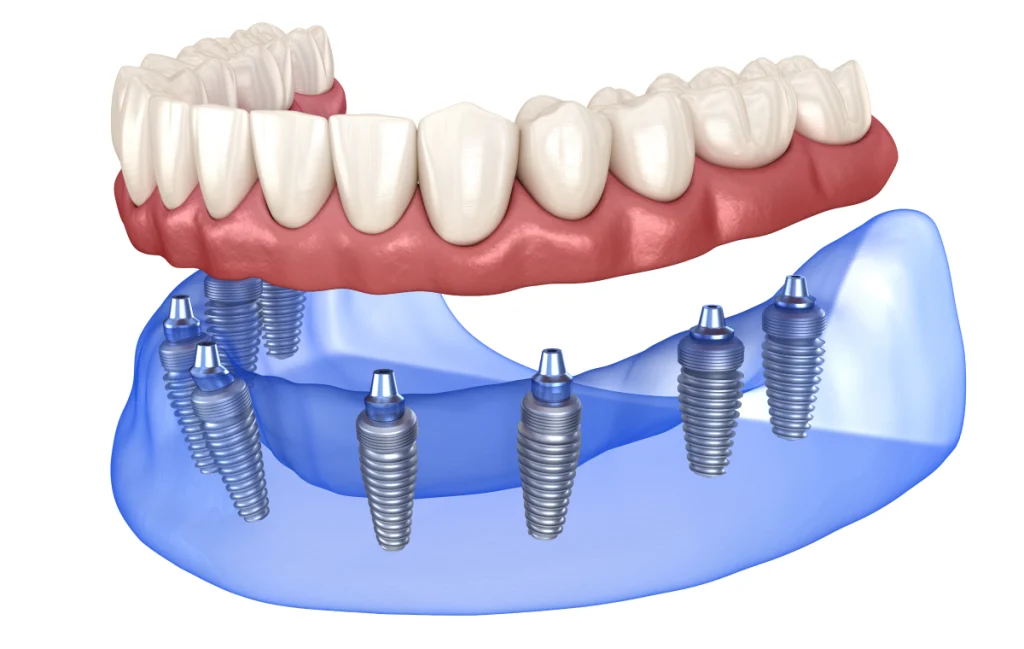

L’All-on-4 / All-on-6 correspond à une approche de remplacement dentaire destinée aux patients présentant une édentation complète ou quasi complète. Concrètement, cette technique repose sur la mise en place d’une prothèse fixe soutenue par des implants dentaires, le plus souvent au nombre de quatre ou de six, positionnés de façon stratégique dans l’os de la mâchoire.

Contrairement aux prothèses amovibles, retirées quotidiennement, l’All-on-4 / All-on-6 s’appuie sur une base fixe solidement ancrée. En effet, les implants jouent le rôle de points de soutien pour une arcade prothétique complète, conçue sur mesure pour chaque patient. De ce fait, cette solution s’adresse principalement aux personnes dont les dents naturelles ne peuvent plus être conservées ou ont déjà été extraites.

La principale différence entre All-on-4 et All-on-6 réside dans le nombre d’implants utilisés pour soutenir la prothèse complète. Dans la technique All-on-4, quatre implants sont positionnés, dont deux implants postérieurs souvent inclinés afin d’optimiser l’ancrage osseux. Cette configuration permet, dans certains cas, d’éviter des procédures complémentaires.

L’All-on-6, quant à lui, repose sur six implants répartis sur l’arcade. Cette option peut être envisagée lorsque le volume osseux le permet et lorsque la situation clinique nécessite une répartition des forces différente.

La pose des implants constitue une étape clé du protocole All-on-4 / All-on-6. Elle se déroule généralement sous anesthésie locale, parfois associée à une sédation selon les besoins. Les implants sont insérés dans l’os de la mâchoire, en respectant le plan établi lors de la phase de préparation.

La mise en place de la prothèse définitive

Une fois la cicatrisation achevée, la prothèse définitive est conçue et ajustée. Elle est réalisée sur mesure, en tenant compte de l’esthétique, de la phonation et de la fonction masticatoire. Le praticien procède à des ajustements précis afin d’assurer un confort durable et une intégration harmonieuse dans la cavité buccale.